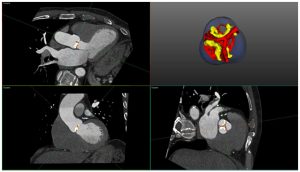

Ecocardiografie și tomografie computerizată cardiacă

Recomandările europene actuale pentru clasificarea ecocardiografică a stenozei aortice (SA) se bazează pe măsurarea gradientului mediu de presiune (parametrul cel mai robust), a vitezei transvalvulare maxime (Vmax) și a ariei valvulare efective (AVA). Deși aria valvulară este teoretic parametrul ideal pentru evaluarea severității, există numeroase limitări tehnice asociate cu calcularea acesteia. Stenoza aortică poate fi clasificată în continuare pe baza indicelui volumului-bătaie (stroke volume index, SVi) atunci când există discrepanțe între parametrii ecocardiografici. Un prag de 35 ml/m2 este acceptat în mod convențional pentru a discerne fluxul scăzut de cel normal.